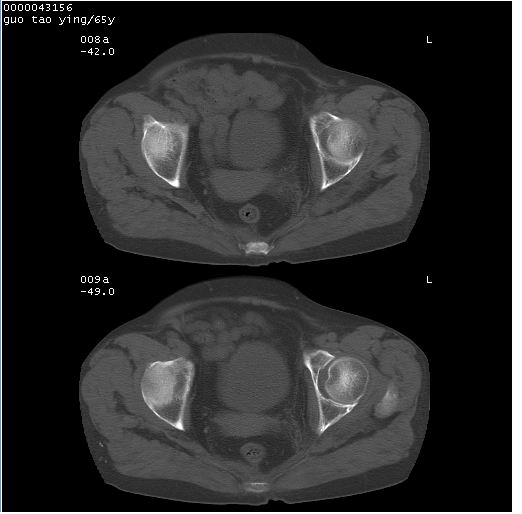

以下是引用黑白光影在2008-1-30 13:22:00的发言:[br]支持左耻骨骨折。[br]未见骶骨骨质明确破坏改变。[br]经楼主提示(勿局限于外伤)。考虑为右侧腹股沟直疝。[br][br][br][br]